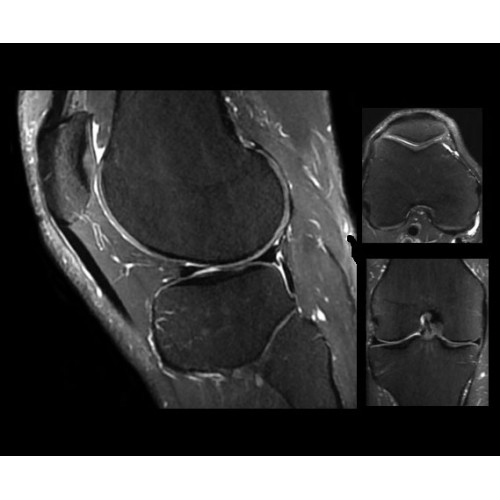

• OrthoWorks — программное решение для визуализации структур опорно-двигательного аппарата с прекрасным контрастированием тканей.

Поле обзора 50x50x50 см и апертура шириной 70 см позволят достоверно визуализировать сложные анатомические области для пациентов с крупным телосложением, например, плечи и бедра. Феноменальная однородность системы SIGNA Architect обеспечивает наиболее широкое поле обзора с улучшенными характеристиками градиентов. Ничто не останется незамеченным.